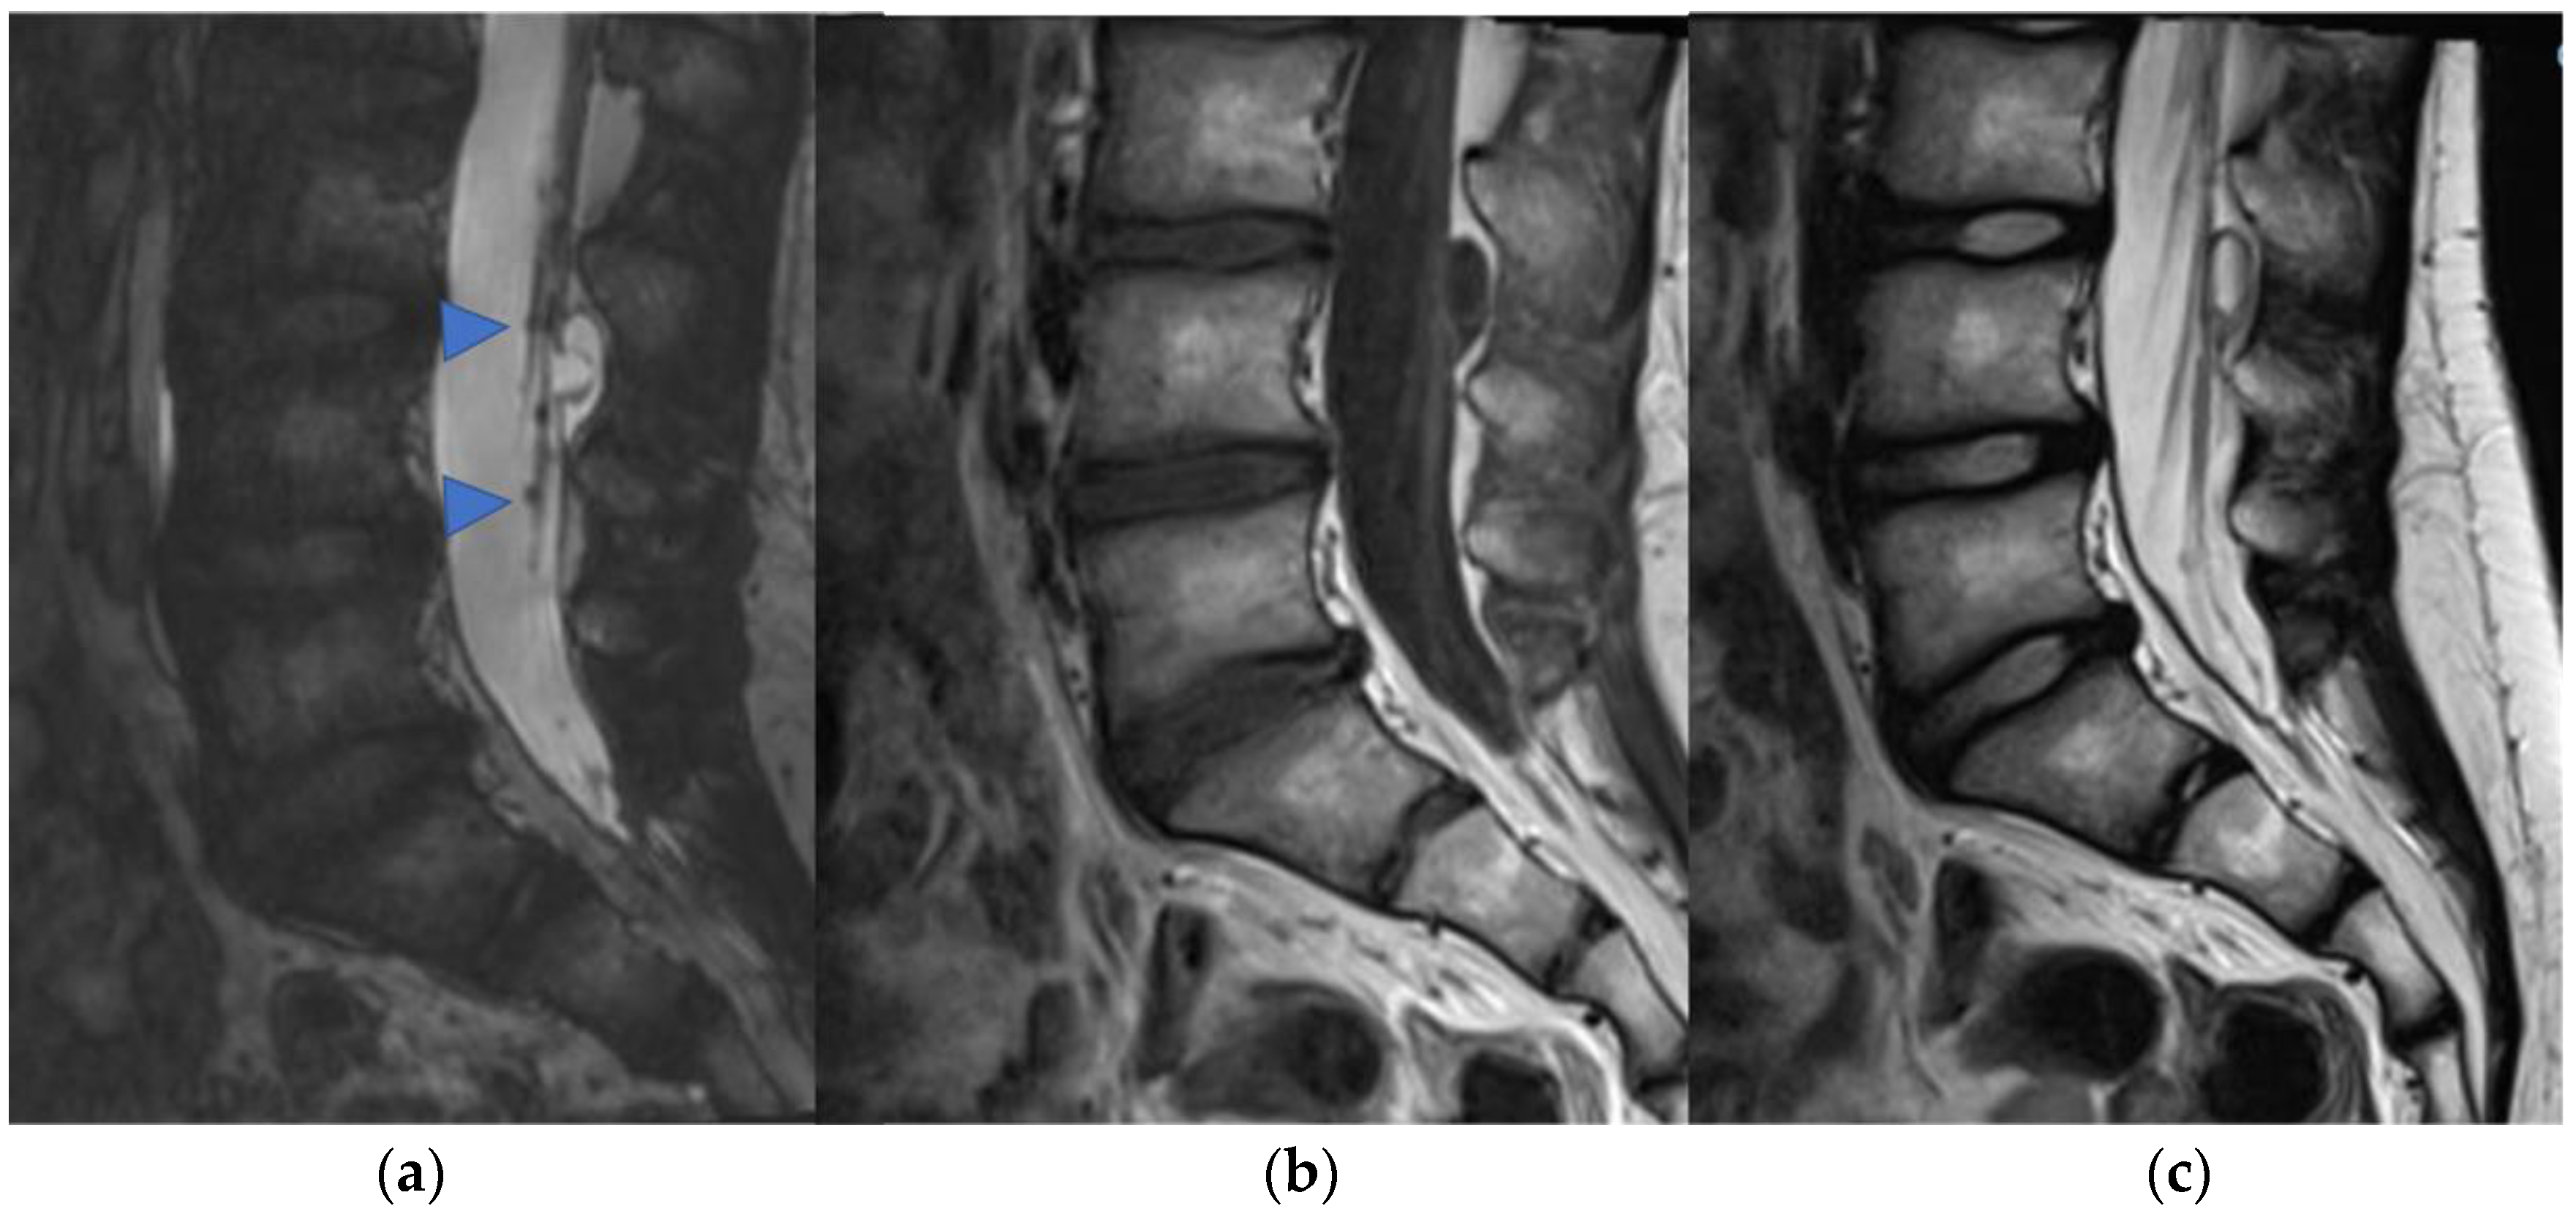

2.2. Diffuse Leptomeningeal Glioneuronal Tumor